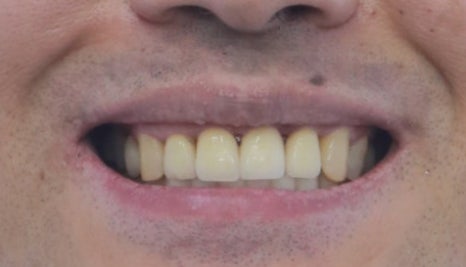

앞니 벌어진 공간이 예쁘게 잘 배열되었습니다.

본인치아를 살리고 교정으로 벌어진 공간을 닫은 상태

교정은 3~4개월이면 끝납니다.

교정!! 이라고 하면

치료기간이 오래걸려서 걱정하는 분 많으시죠?

이렇게 부분교정을 할 경우

아주 짧은 시간 안에 치료가 마무리됩니다.

부분교정은 비용도 상대적으로

저렴하다보니

부담없이 시도해볼 수 있습니다.